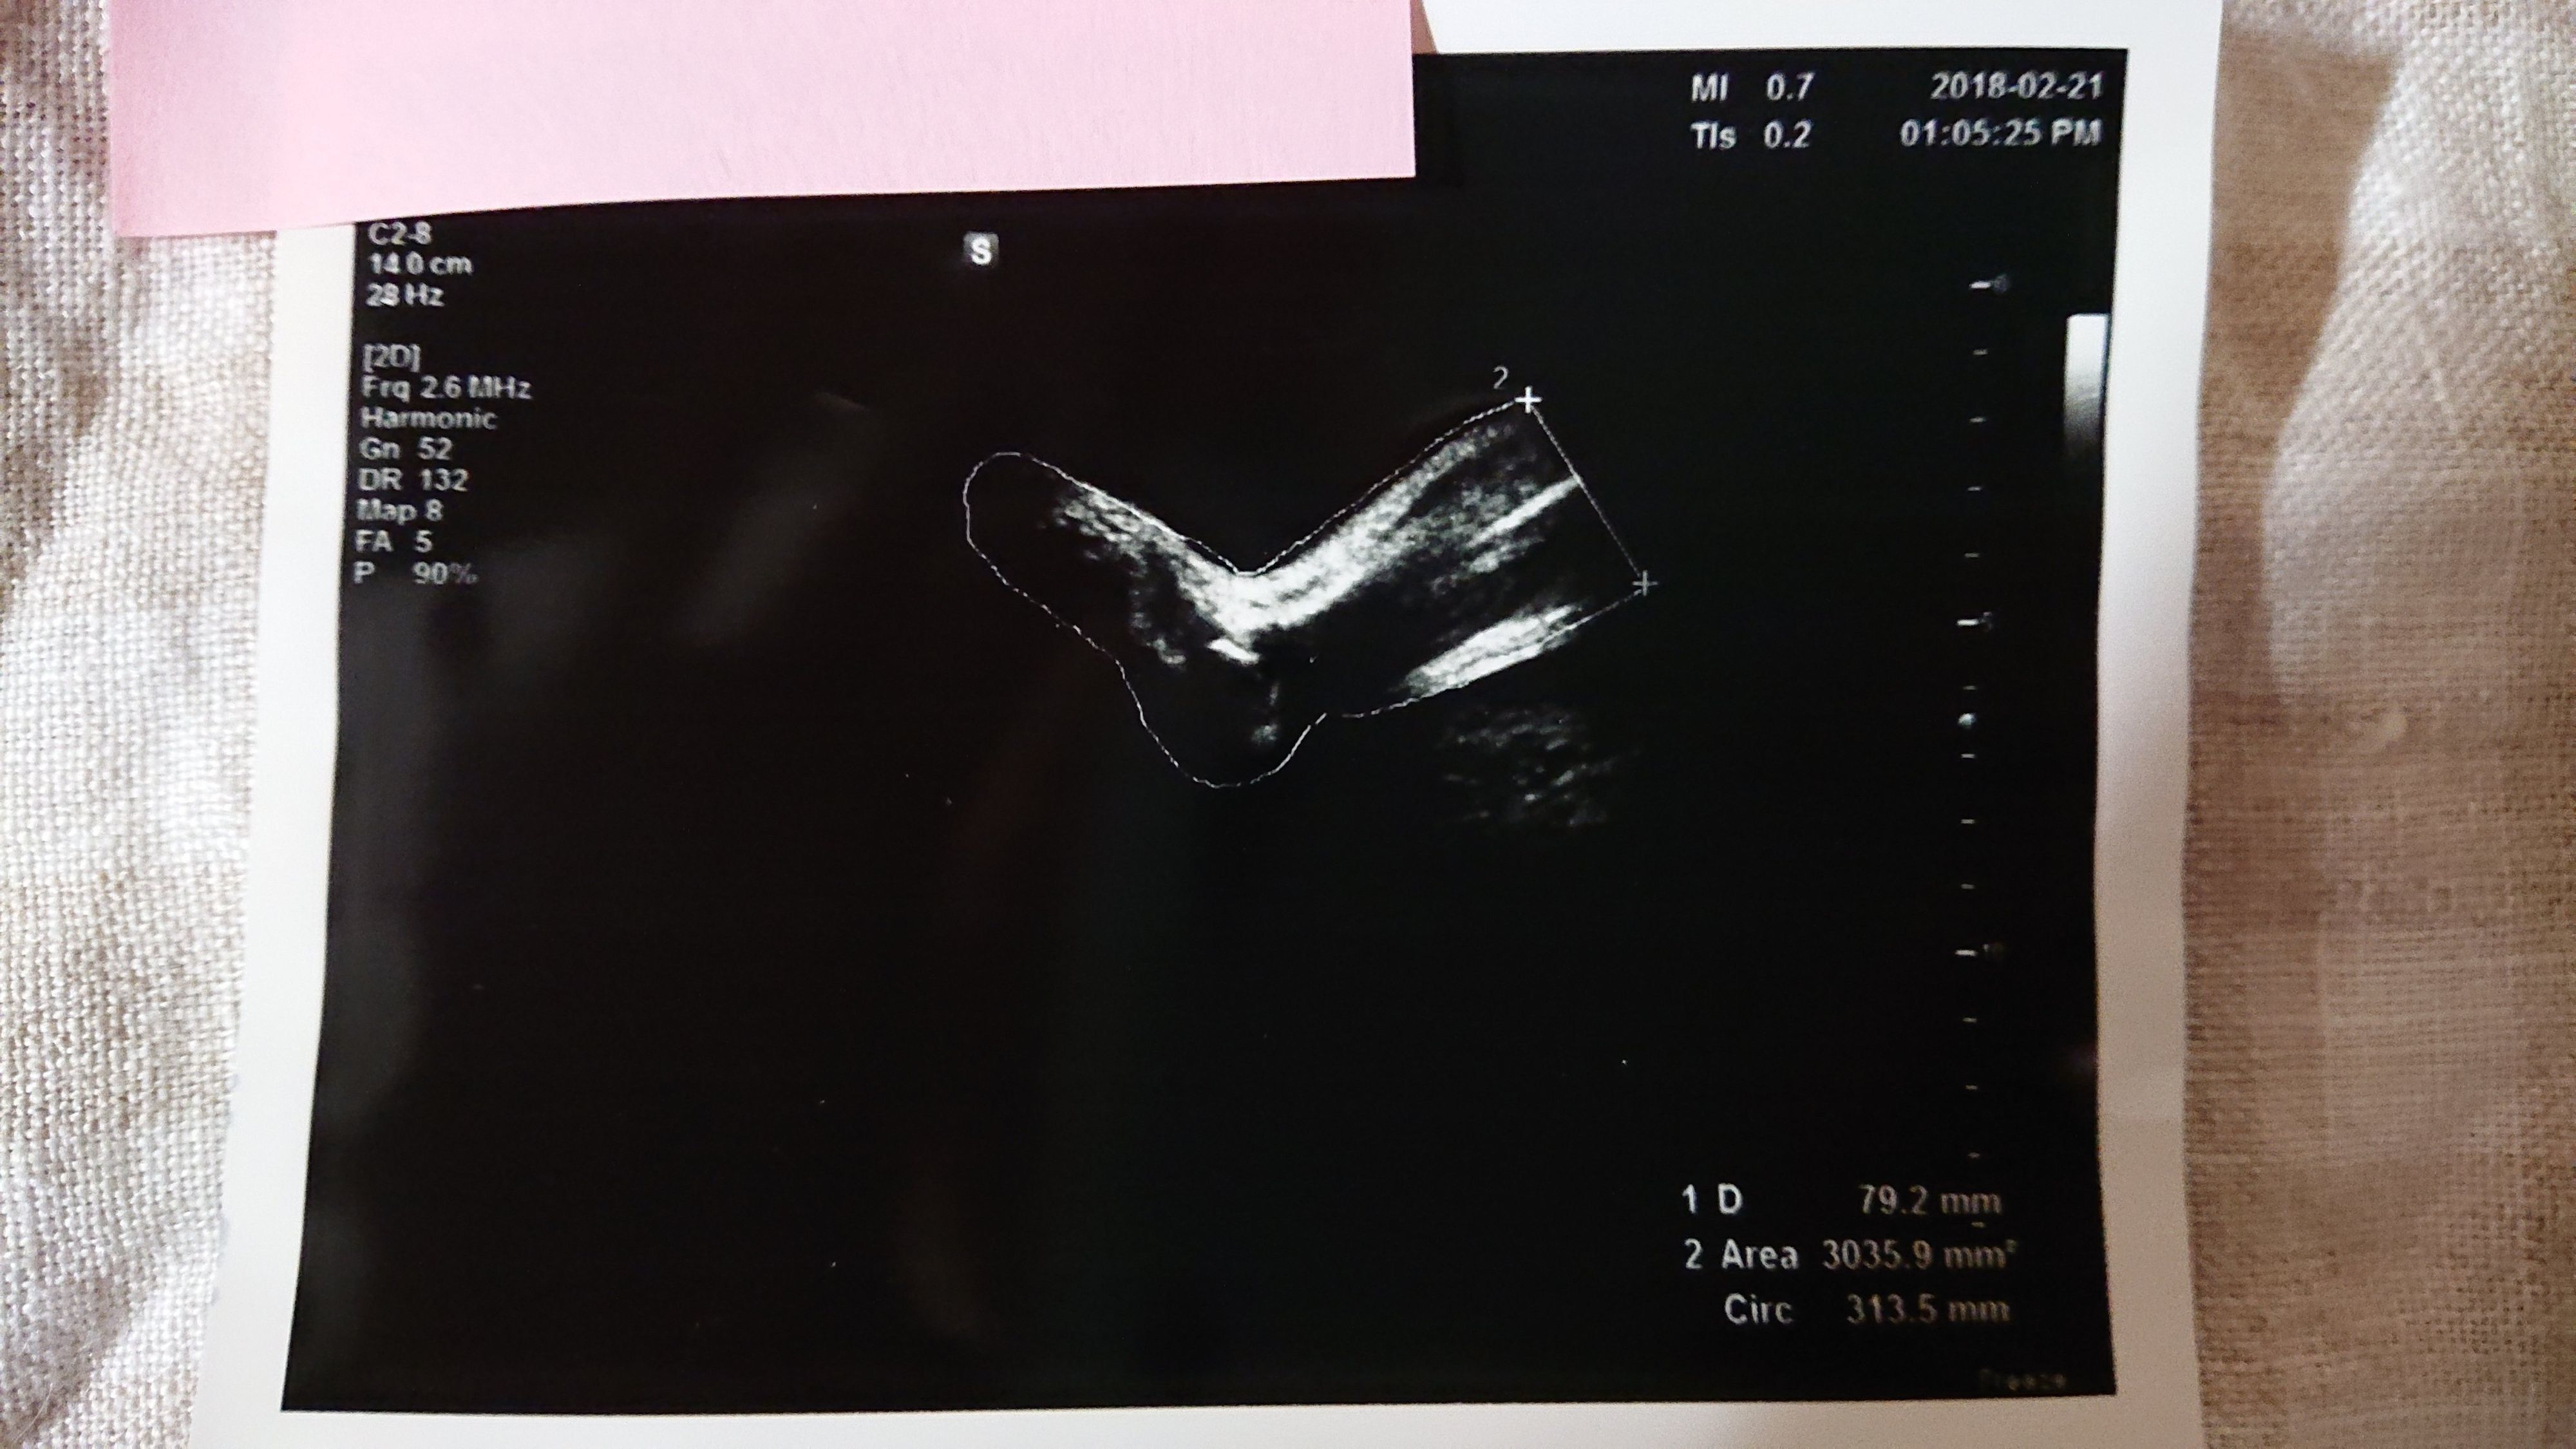

《妊娠36週目のエコー写真》

帝王切開手術の予定日から1週間前、妊娠36週目のエコー写真です。妊婦健診では「逆子が戻っていますように」と毎回願うのですが、この時も戻らず。でも、医師や看護師から「出産直前にも最終チェックするからね。その時に急に戻ってる赤ちゃんだっていたことあるから」と励まされました。切迫早産で24時間点滴が繋がっている状態では逆子体操もできないので、「戻れ~、戻れ~」と、願う事しかできませんでした。エコー写真は赤ちゃんの足です。